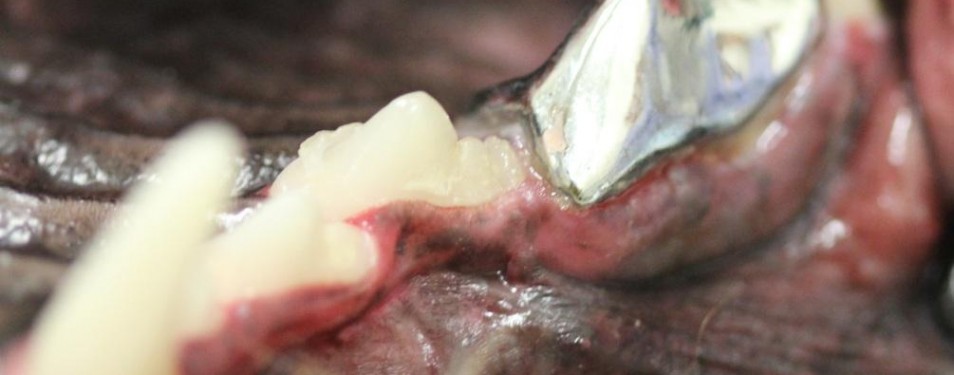

Canine Crowns